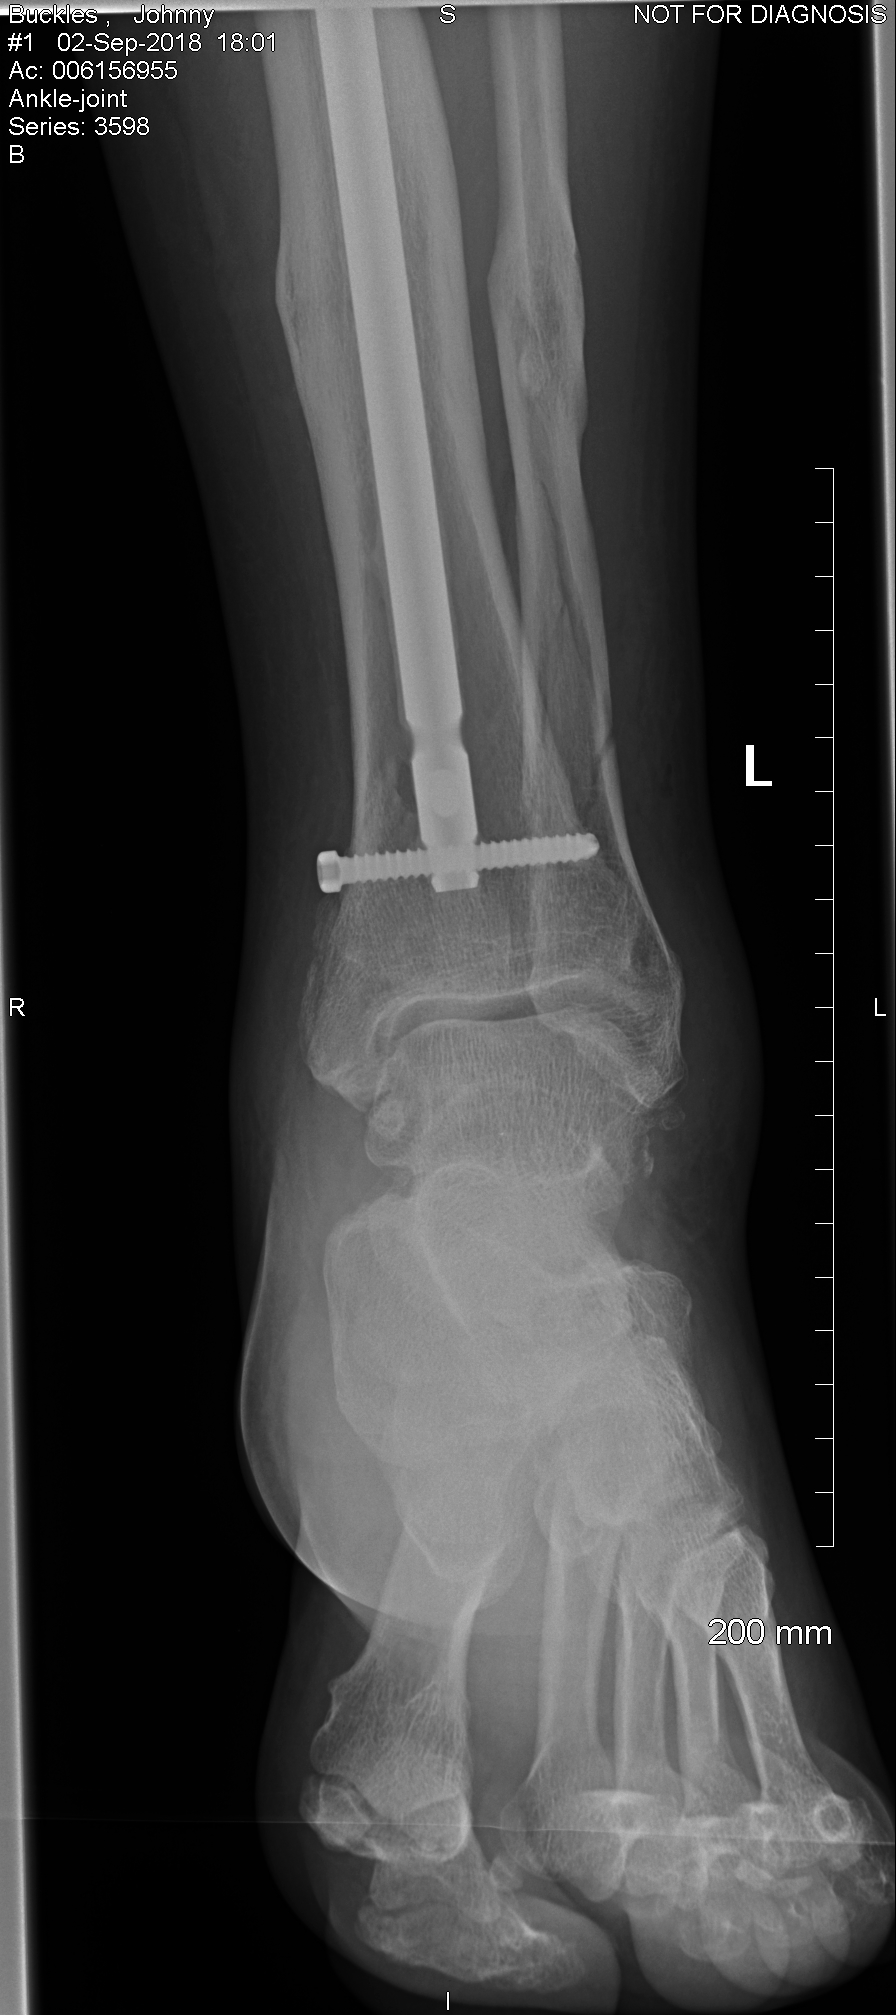

this is pics of my broke leg that I have droke twice now.